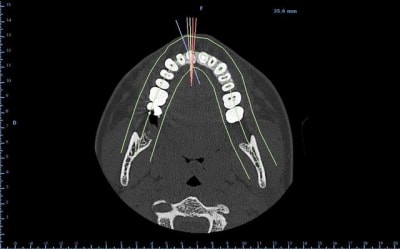

Tu n’a pas un couloir suffisent entre les corticales pour placer un implant avec des vis à compression ?

bon, autre truc plutôt défavorable au greffon ramique...je viens de vérifier: contact des apex de 38 et 48 avec le NDI...et comme les dds ont suffisamment de place...on laisse tranquillement évoluer...

sincèrement...j'ai pas trop envie de me casser la tête...

un greffon type puros ou biobank en bloc me semble être un bon compromis....

juste des particules d'os de synthèse...quid de la stabilité réelle du volume par rapport au bloc?

je sais que 17 ans c'est jeune...mais entre la greffe (bien 6 mois de cicat) la pose de l'implant (avec 3 ou 4 mois d'ostéointégration) on va vite être à 18 voir 19 ans...et là, je pense qu'on peut concevoir un ttm implantaire...non?